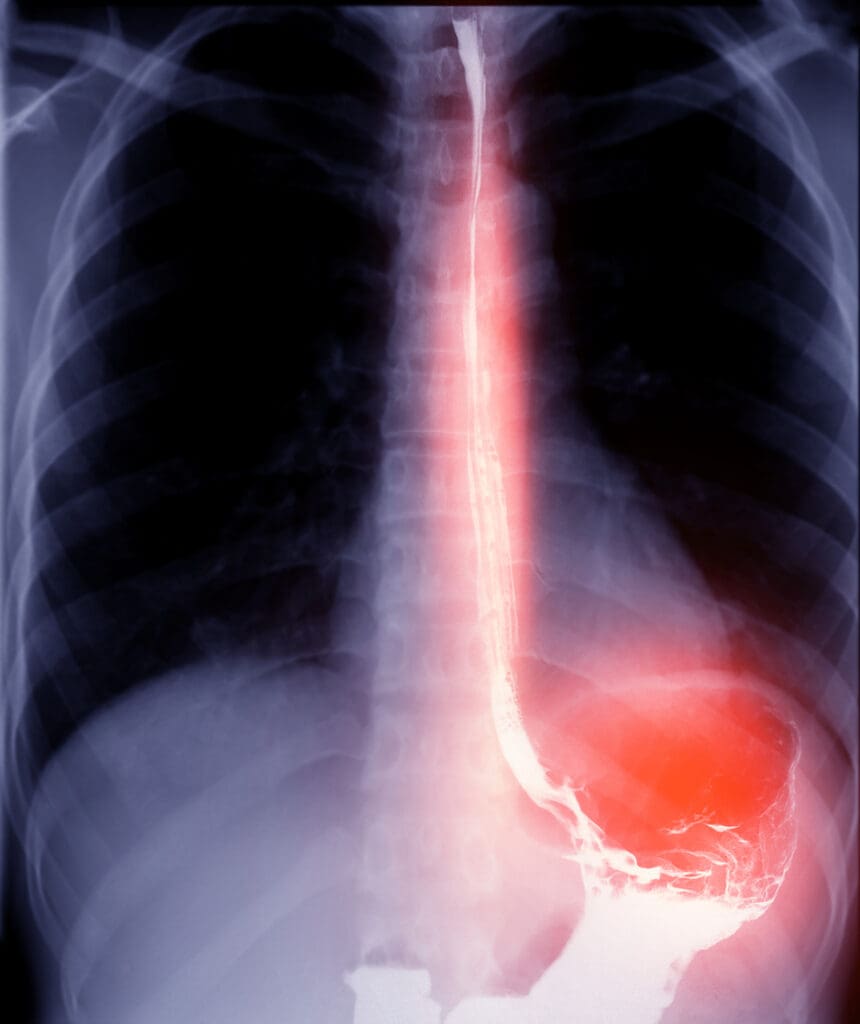

Swallowing Difficulty Dysphagia